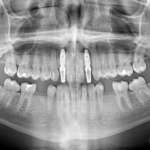

Chirurgia guidata: strumento indispensabile nella pianificazione chirurgica e protesica

In questo case report realizzato dal Dott. Gabriele Vaccaro, viene descritto un intervento di riabilitazione implantare di un dente singolo effettuato con pianificazione digitale....